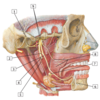

#1 - middle meningeal artery

#2 - buccal artery

#3 - external carotid artery

#4 - superior thyroid artery

#5 - common carotid artery

#6 - internal carotid artery

#7 - facial artery

#8 - maxillary artery

#9 - superficial temporal artery

#1 - pterygoid plexus

#2 - superior laryngeal vein

#3 - middle thyroid vein

#4 - inferior thyroid veins

#5 - subclavian vein

#6 - internal jugular vein

#7 - common trunk for facial, retromandibular, and lingual veins

#8 - external jugular vein (cut)

#9 - retromandibular vein

#10 - superficial temporal vein and artery

#1 - parotid gland

#2 - main trunk of facial nerve emerging from stylomastoid foramen

#3 - sternocleidomastoid muscle

#4 - external jugular vein

#5 - temporal branche of facial nerve

#6 - parotid duct

#7 - masseter muscle

#8 - facial artery and vein

#9 - cervical branch of facial nerve

#1 - sphenopalatine artery

#2 - posterior superior alveolar artery

#3 - descending palatine artery in pterygopalatine fossa

#4 - inferior alveolar artery

#6 - deep temporal arteries and nerves

#5 - middle meningeal artery